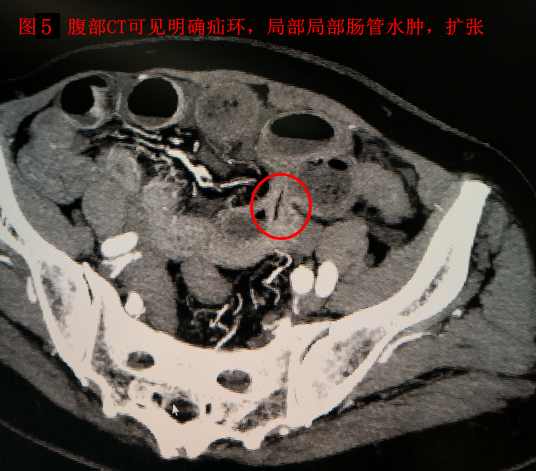

患者:李##,男性,93岁,家住北京昌平天通苑社区,既往患有阿尔兹海默征(俗称“老年痴呆”),无法正常交流。入院前2天出现腹痛、腹胀、恶心、呕吐,自行应用甘油灌肠剂治疗后未见缓解。后出现发热、停止排气排便,就诊于外院,行腹部CT考虑为肠梗阻,给予输液治疗后无效,症状加重,进一步就诊于我院急诊外科,入院时患者神志淡漠,急性痛苦面容,腹部略膨隆,全腹部压痛、反跳痛及肌紧张,患者因不能正常交流,不能描述压痛最重部位。听诊肠鸣音弱。外院腹部CT阅片可见腹腔游离气体,广泛肠道肠壁肿胀,并可见气液平面,考虑为消化道穿孔引起的腹腔感染,并发肠梗阻。血象明显升高(C反应蛋白>200mg/L,白细胞 14.95×10^9/L,中性粒细胞绝对值 12.99×10^9/L,中性粒细胞百分比 87.00%)。因外院腹部CT胶片显示不清,不能明确穿孔部位。急诊复查腹部CT,阅片可见肝周游离气体明确,消化道穿孔诊断明确(见图1。腹腔内肠管肠壁肿胀,可见多发气液平面,考虑为继发性肠梗阻。除外最常见的胃十二场溃疡穿孔及阑尾穿孔。可见左下腹肠道内“枣核”影(见图2,局部肠管肠壁肿胀最明显明显,并可见少量积液。考虑枣核所致小肠穿孔可能大。追问病史家属确认2天前患者进食大枣粥时不慎将枣核吞咽,根据腹部CT提示枣核影位置,反复腹部查体,通过观察患者表情,确认枣核所在部位为压痛最明显部位。综合患者病史、查体及辅助检查结果,考虑患者为肠道异物(枣核)所致小肠穿孔可能性较大。患者如不紧急实施手术治疗,腹腔感染继续加重,会危及老人生命。但患者超高龄,病程较长,全身状况差。心肺脑等重要脏器功能无法完全评估,且患有老年痴呆,围手术期无法配合治疗,围手术期风险极高。充分向患者家属交待手术的必要性及风险后,患者家属表示理解。急诊行手术治疗,术中探查,因患者既往上腹经腹直肌切口下方可见乙状结肠及大网膜粘连,乙状结肠与盲肠、末端回肠及右肝下方粘连,分离粘连,仔细探查腹腔。胃及十二指肠未见明显异常,结肠未见明显病变,距回盲部约160cm处可见小肠局部大量脓苔,肠壁可见异物(枣核)刺穿肠壁(见图34,局部炎症较重,肠壁糜烂,局部腹腔及盆腔可见淡黄色脓液,量约400ml